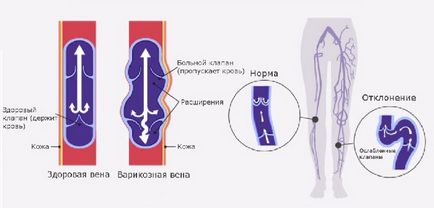

Visszér. Ez hatással van a vénás rendszer a személy. A betegség oka a gyengeség a érfalak a vénák, és patológiája a szisztémás keringésbe, ami megnövekedett nyomás a vénás rendszerben.

Vizuális módosítása hajók a bőr, visszértágulat az alsó lábszár és a láb, a vaszkuláris pályák jelezheti mind krónikus, mind akut vaszkuláris betegségek (thrombophlebitis, lymphangitis, és így tovább. D.).